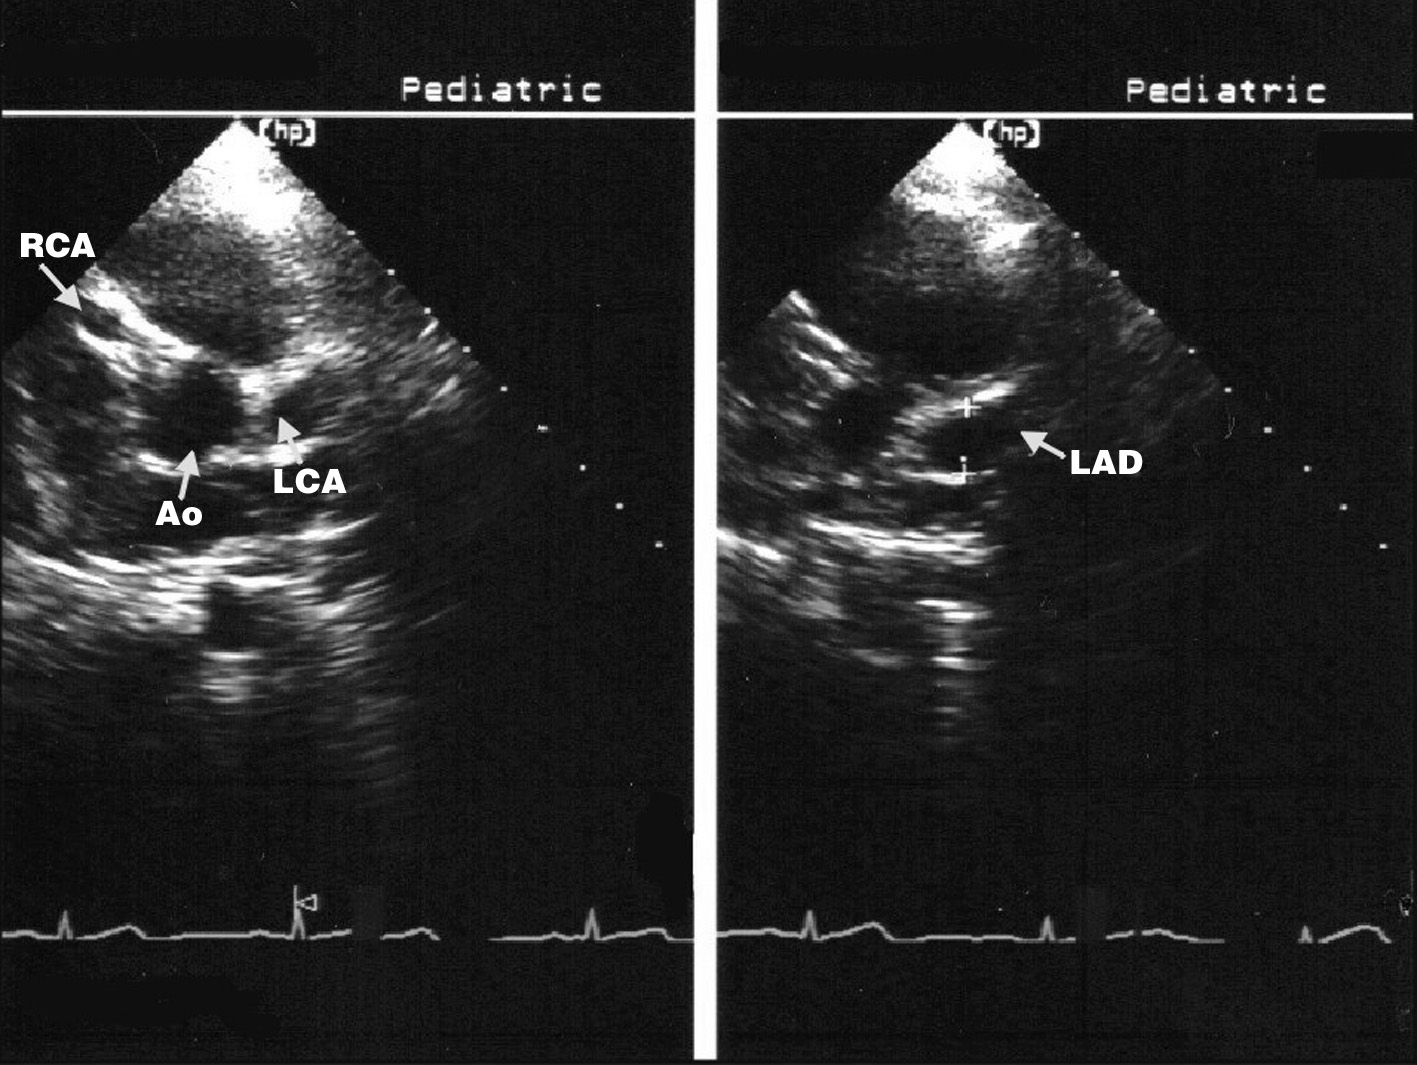

Kawasaki disease early findings consist of congestive heart Kawasaki Disease Heart Valve Coronary artery involvement is the. Kawasaki disease is the second most common vasculitis in childhood (the most common being iga vasculitis). Kawasaki disease (kd) is now a common cause of acquired heart disease in children. Kawasaki disease is an acute vasculitis of childhood that leads to coronary artery aneurysms in ≈25% of untreated cases. Kawasaki disease can also cause inflammation. Kawasaki Disease Heart Valve.

Recent updates on echocardiography and ultrasound for Kawasaki disease Kawasaki Disease Heart Valve Valvular insufficiencies, particularly of mitral or tricuspid valves, are often observed in the acute phase of kawasaki disease due to valvulitis or myocarditis. Coronary artery involvement is the. Kawasaki disease is an acute vasculitis of childhood that leads to coronary artery aneurysms in ≈25% of untreated cases. Kawasaki disease (kd) is now a common cause of acquired heart disease in. Kawasaki Disease Heart Valve.